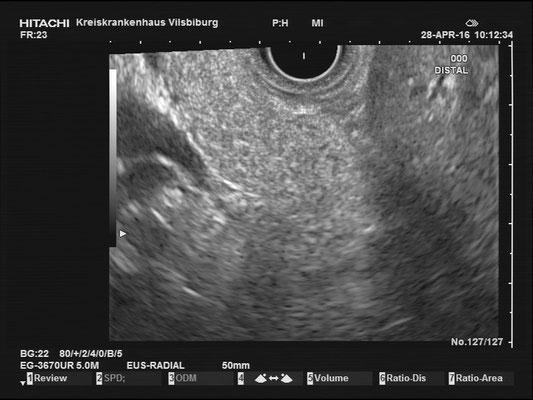

The images above depict a thorough inspection of the pancreas, as seen in an radial EUS Examination. We begin (hopefully ;) bei identifying the uncinate process between the golden V, which is formed by the aorta/V. cava and the mesenteric vessels. After spotting die usually hypoechoic ventral pancreatic root, the duodenal papilla can be identified (for a more detailed approach, please visit "Learning Endosono"). By following the splenic vein, the body and tail of the pancreas can be examined.

The most observant viewers will have noticed that not all images above depict normal findings but some abnormalities. (my bad ;)